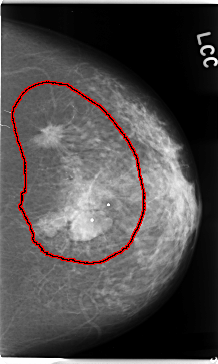

C_0112_1.LEFT_CC

LEFT_CC LINES 4720 PIXELS_PER_LINE 2832 BITS_PER_PIXEL 12 RESOLUTION 50 OVERLAY

FILE: C_0112_1.LEFT_CC.OVERLAY

TOTAL_ABNORMALITIES 1

ABNORMALITY 1

LESION_TYPE MASS SHAPE IRREGULAR MARGINS SPICULATED

ASSESSMENT 5

SUBTLETY 5

PATHOLOGY MALIGNANT

TOTAL_OUTLINES 1

BOUNDARY